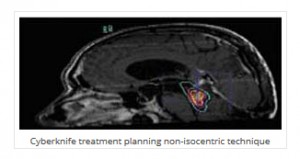

Το CyberKnife® συνδυάζοντας τα πλεονεκτήματα της μεγάλης ακρίβειας εντόπισης, εύκολης και αναίμακτης προσπέλασης και τη δυνατότητα μη ισοκεντρικής ακτινοβολίας, φαίνεται να αποτελεί τη λύση επιλογής σε πολλές περιπτώσεις γλοιωμάτων. Εφαρμόζεται επί υποτροπής του όγκου μετά από προηγηθείσα κλασσική ακτινοθεραπεία αναγκαίας για την κάλυψη των συνήθως ανωμάλου σχήματος γλοιωμάτων.